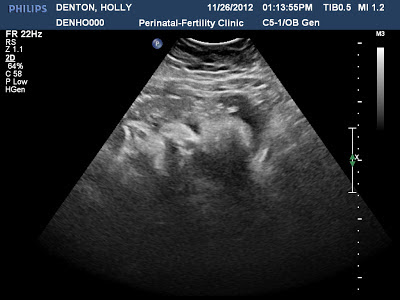

Yes GERMS! On Monday I was fine went to my high risk appt and had a ball with everyone in the office like always after I leave there I feel great because I have reassurance and feel safe. Then come later that night throat kind of itched and then BAM full on sick!! I have no idea what is wrong with me but it went straight to my chest and the next morning I had to go in to the OB because I was on my freaking death bed! I was so scared that it would be like last time and I would end up getting THAT sick again and frankly now I realize I am traumatized from what happened in July. Luckly after two antibiotics I am feeling better today. So on with the doctor's appts! Monday baby was wonderful and scored great had a flawless sono with BPP and was a hefty 5 pounds 12 oz her NST was wonderful and I was switched over to heparin twice a day to get me ready for delivery incase it happens sooner then expected. So the second appt was the next day because I was sick I went in and they gave me two shots of rocephen and then baby was tachy but so was I so I think it was stressing her out. So I was stuck on the monitor until she improved. At first she was non-reactive but as soon as I drank some juice she was reactive and heart rate was better so they said I could go home to sleep because I did not sleep the whole night before but maybe 30 minutes to a hour at a time. They also sent me home on keflex. The horrid thing about being sick when you are pregnant is you can't take ANYTHING!! Especially in the third trimester everything that actually works is off limits. Not only that is I am coughing and sneezing and vomiting because of all the flem which is not good for someone with a incompetent cervix. My pelvis hurts so bad from all the muscle strain its unbelievable and hard to walk. But I am now over 34 wonderful weeks! Next goal is 36 weeks and then its BABY! Only 3 weeks until my c-section???!!! WHAT? I may actually make this? I might actually TAKE home my baby with me? We are ready for you Kinley Raye keep hanging in there baby we will make you happy for the rest of your life!